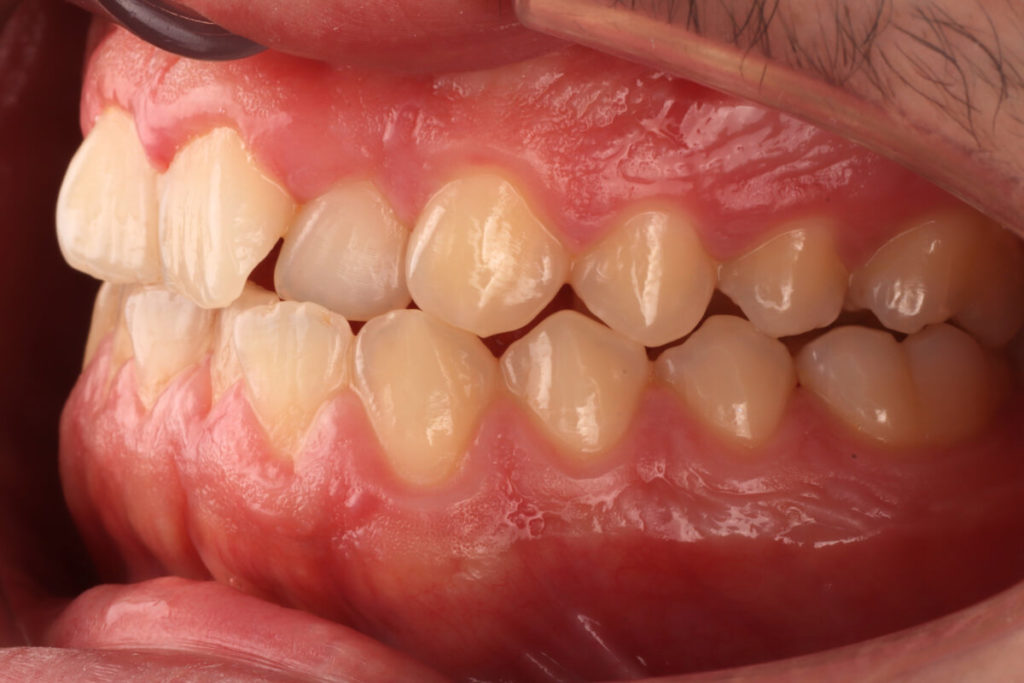

SITUACIÓN INICIAL

CLASE I MORDIDA CRUZADA EN LATERALES

• Clase I con mordida cruzada en los incisivos laterales.

• Apiñamiento moderado en el arco superior e inferior.

• Desplazamiento de la línea media superior.

• Arco normal con necesidad de expansión.